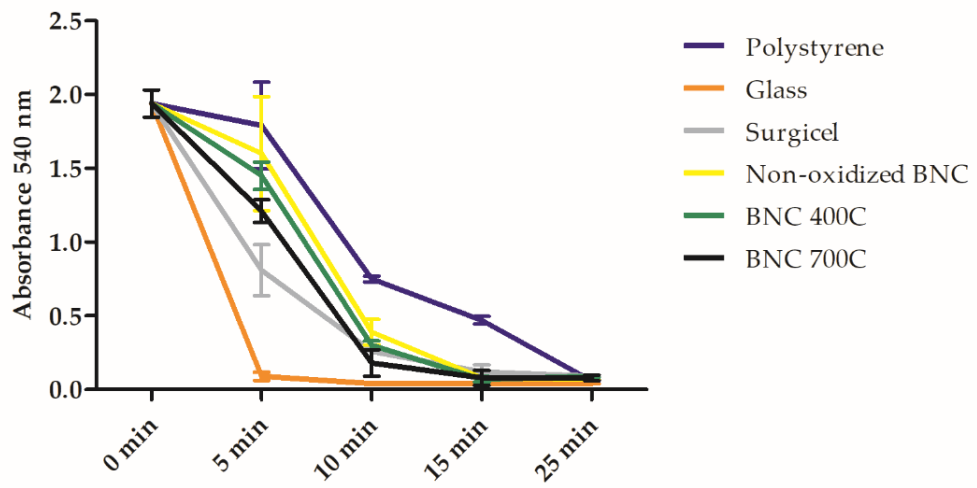

3.9. Biological Assays and Hemostatic Behavior of BNC Membranes